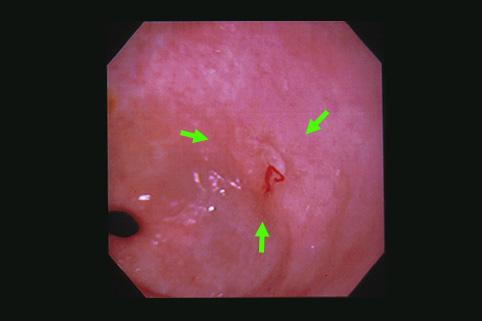

질환(병리주체)의 분류 악성 상피성종양/선암

부위(장기별) 위(부위)/전정

검사방법 내시경

종양의 육안분류 0형(표재형)/IIc형(IIc)

종양의 최대경(밀리미터) 1~9

종양의 심달도 m